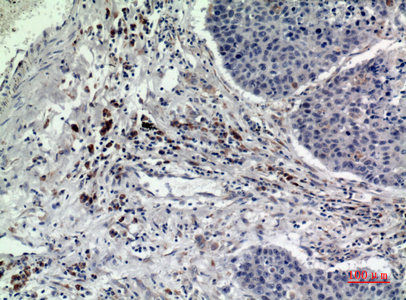

WB,IHC-P,IF-P,IF-F,ICC/IF,ELISA

WB 1:500-1:2000, IHC-P 1:100-1:300, ELISA 1:20000, IF-P/IF-F/ICC/IF 1:50-200